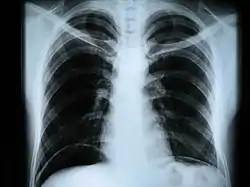

Наиболее часто термин относится к медицинскому неинвазивному исследованию, основанному на получении суммарного проекционного изображения анатомических структур организма посредством прохождения через них рентгеновских лучей и регистрации степени ослабления рентгеновского излучения.

Сейчас рентген грудной клетки часто используется для диагностики заболеваний, вызванных инфекциями лёгких. Однако этот метод оказался малоэффективен для обнаружения ранних стадий вирусных пневмоний, вызванных COVID-19.

Американские исследователи во главе с профессором Университета штата Огайо изучили рентгеновские снимки 630 пациентов с подтверждённым коронавирусом и выраженными симптомами. В 89 процентах случаев на рентгене не было заметно никаких отклонений, или они были незначительными. Практика врачей ГКБ №40 в посёлке Коммунарка, которые первыми приняли на себя удар пандемии в России, также подтвердила эти выводы. Тем не менее, на более поздних этапах с помощью рентгенографии можно получить точные и качественные результаты. Именно поэтому в текущей ситуации особенно актуальны портативные аппараты, которые можно применять в палатах пациентов в тяжёлом состоянии[3].

В настоящее время рентгенография остаётся основным методом диагностики поражений костно-суставной системы. Важную роль играет при обследовании лёгких, особенно в качестве скринингового метода. Методы контрастной рентгенографии позволяют оценить состояние внутреннего рельефа полых органов, распространённость свищевых ходов и др.

- рентгенография грудной клетки — инфекционные, опухолевые и другие заболевания,